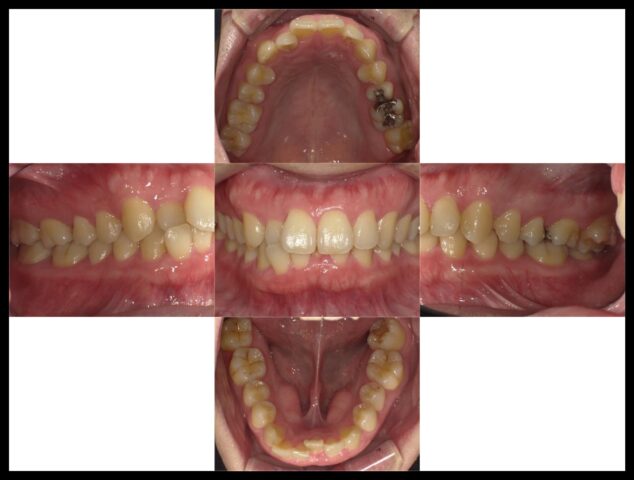

症例紹介

before

after